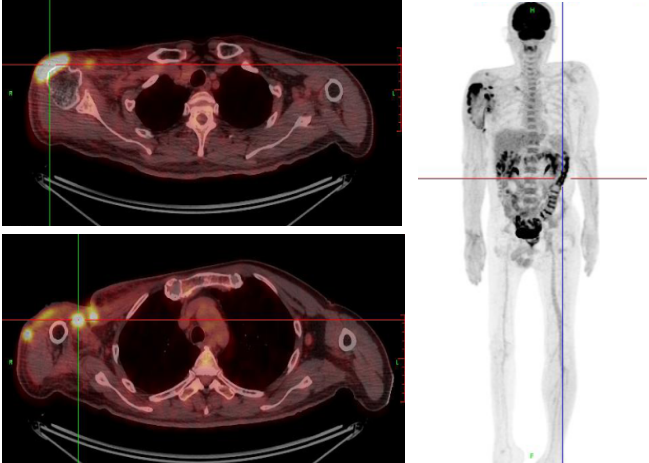

先后行6次全麻下右腋窝清创术+负压吸引术,2020.4.16我院病理提示右上臂皮下组织,大片坏死组织内可见异型细胞增生及浸润,结合免疫组化结果,诊断为NK/T细胞淋巴瘤。免疫组化:ALK-、CD2+、CD20-、CD3+、CD30±、CD5+、CD56-、CD7+、CK-、C-myc-、EBER+、GrB+、Ki-67 85%、P53-、PAX-5-、TIA-1+、β-catenin-。PET/CT(见图1):1.右腋窝清创术后,右肩关节周围、右腋窝区、右肩背部及右臂近段软组织结构紊乱,局部肿胀、增厚、不连续,皮下脂肪密度不均匀增高,可见条片状软组织影,放射性摄取显著增高,SUVmax 19.21。腋窝区部分软组织缺失。2.结、直肠肠壁呈弥漫性放射性摄取增高,SUVmax 13.65。

图1、PET/CT检查